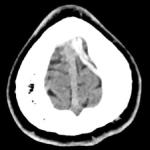

Lymphome de Hodgkin à localisation cutanée spécifique

Un homme de 25 ans consulte pour des symptômes respiratoires incluant une dyspnée, une orthopnée et une toux, accompagnés de l’apparition...